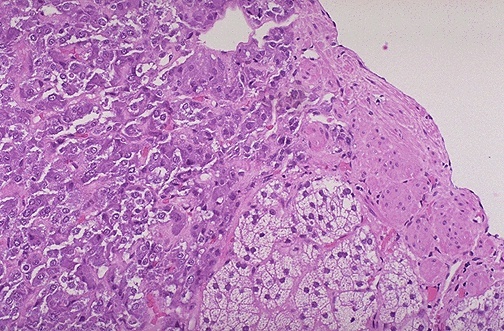

A diffusely enlarged thyroid gland associated with hyperthyroidism is known as Graves disease. At low power microscopically, note the prominent infoldings of the hyperplastic follicular epithelium. In this autoimmune disease the action of thyroid stimulating immunoglobulins (TSI’s) predominates over that of thyroid growth immunoglobulins (TGI’s).

Shown at high power, the tall columnar thyroid epithelium with Graves disease lines the hyperplastic infoldings into the colloid. Note the clear vacuoles in the colloid next to the epithelium where the increased activity of the epithelium to produce increased thyroid hormone has led to scalloping out of the colloid in the follicle.